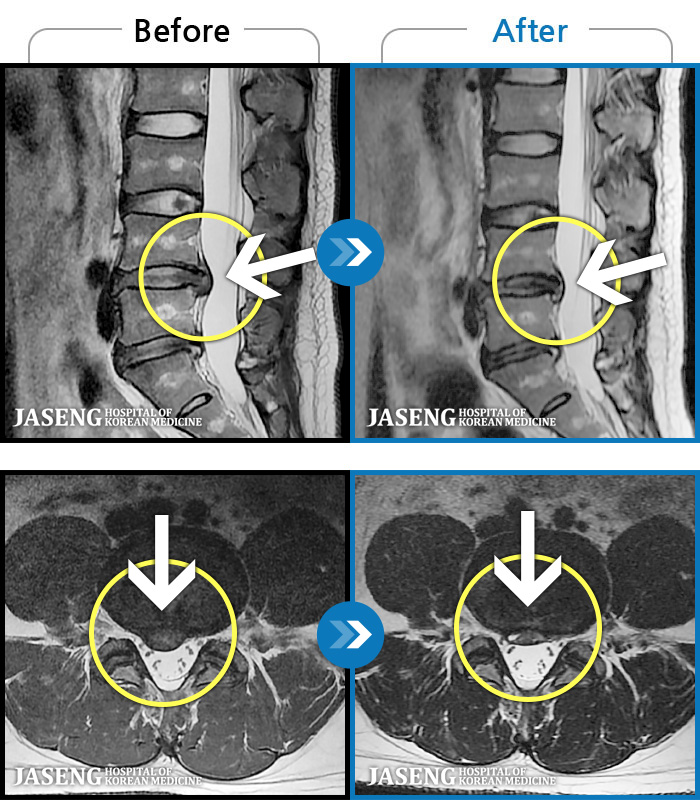

64 MRI ũ ʸ Ȯϼ.